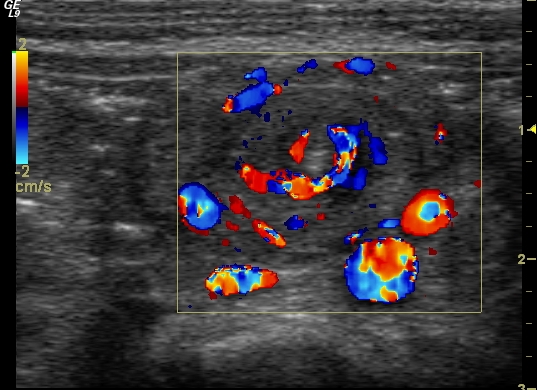

Malrotation-volvulus. During the normal development of the intestinal tract, the intestinal loops make three 90 degree clock-wise rotations around the mesenteric superior artery (MSA.) If this rotation only partially occurs during the embryonic development the intestines remain in a non-rotational or malrotational position, the mesenteric root will be shorter and the cecum will be weakly attached. This anatomic positioning can be symptom free throughout a lifetime, but it predisposes for volvulus. Volvulus can occur at any age, but it is most frequent in the first months of life, when it abruptly occurs with acute bilious vomiting. In this state the intestines around the mesenteric root twist, end up in a complete obstruction that can lead to a rapid death of the intestines. Ultrasonography can depict the mesenteric superior vein (MSV) coiled up around the MSA, so called “whirlpool”-sign.

14. “Whirlpool” sign The mesentery and the superior mesenteric vein, as it coils around the superior mesenteric artery. Volvulus. US exam.